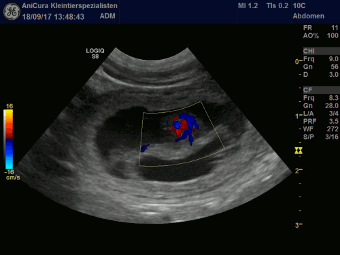

| 18.09.2017 |

| Uaine ist schwanger. Die Ultraschallbilder beweisen es. |